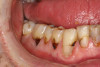

(2.) Lingual and facial maxillary views of 5-year-old patient, 1 year after caries attenuation with SDF. The parents were not concerned about the black staining.

Figure 2

(3.) Lingual and facial maxillary views of 5-year-old patient, 1 year after caries attenuation with SDF. The parents were not concerned about the black staining.

Figure 3